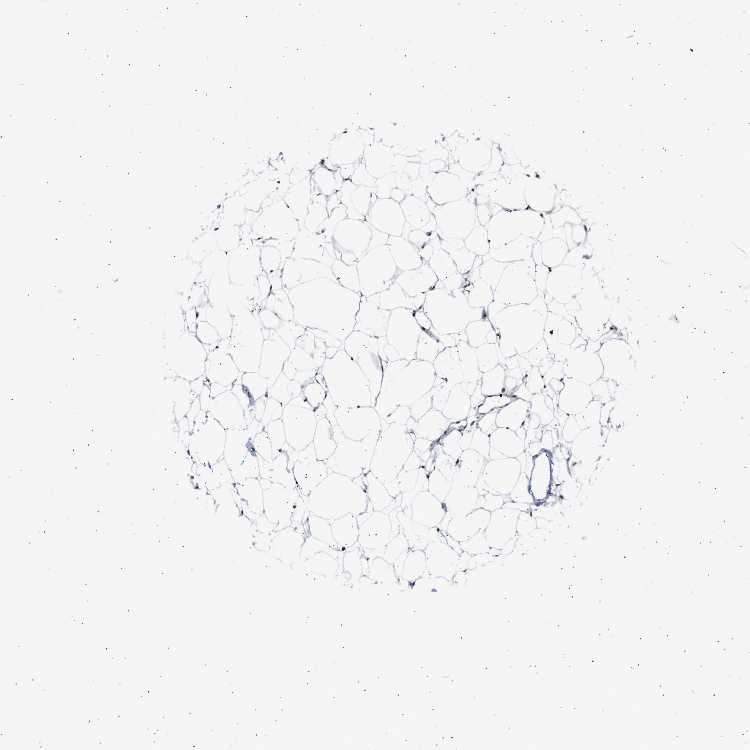

ADIPOSE TISSUE - Antibody stainingi

Antibody staining in the annotated cell types in the current human tissue is reported as not detected, low, medium, or high, based on conventional immunohistochemistry profiling in selected tissues. This score is based on the combination of the staining intensity and fraction of stained cells.

Each image is clickable and will lead to virtual microscopy that enables deeper exploration of all samples and also displays staining intensity scores, fraction scores and subcellular localization as well as patient and tissue information for each sample.

Antibody HPA019824Antibody CAB015201

Adipocytes Not detectedMedium